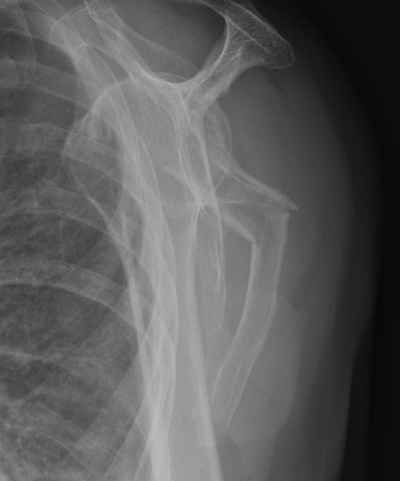

Medial displacement